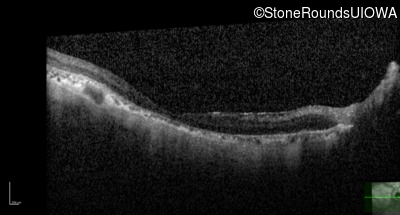

AR Stargardt Disease (IIA)

Age at visit:

72 years

OD

OS

20/200

AR Stargardt Disease

ABCA4

Gly607Arg GGG>AGG

IVS30+1321 A>G

AR